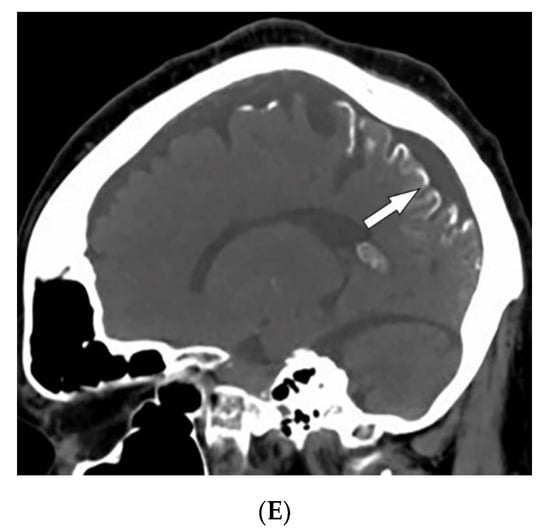

4.1. Melanotic Melanoma

| Melanotic melanoma | ABCDE features | Enhancing lesions if they contain a sufficient amount of melanin Multiple well-defined lung nodules |